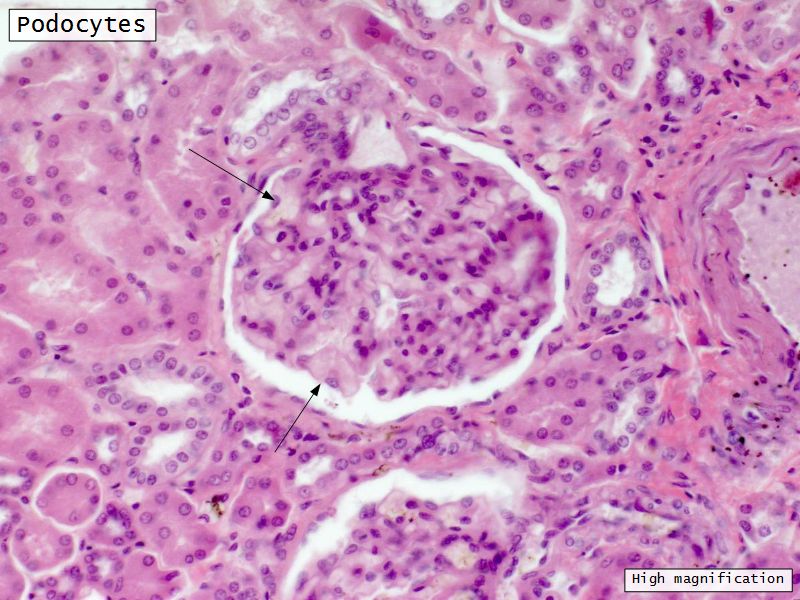

Podocytes

• Visceral layer of epithelium

• Protrude into capsular space

• Attached to basement membrane

• Long cytoplasmic extensions

• Primary processes

• Secondary processes

• Podocyte feet

• Tightly spaced

• Filtration slits 20 - 30 nm wide